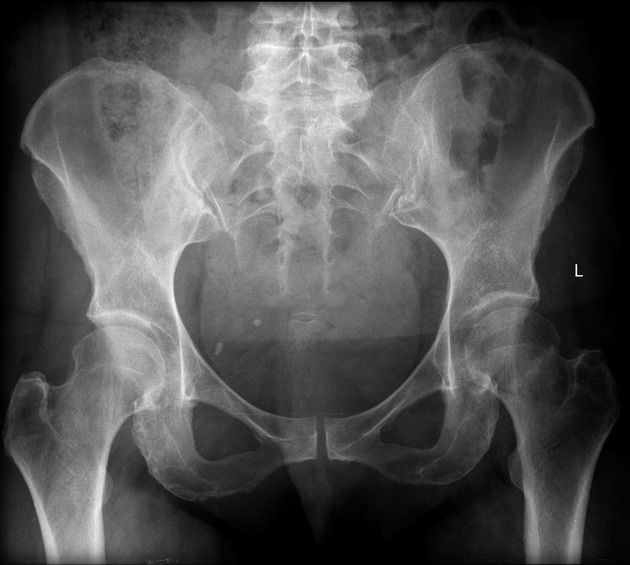

Example 2

Diagnosis

Osteoarthritis of the Hip (right)

Image 2:Feger, J., Niknejad, M. Osteoarthritis of the hip. Reference article, Radiopaedia.org. https://doi.org/10.53347/rID-81200